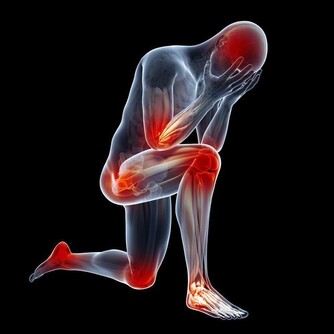

二、男性出現這2種異常時,需警惕尿毒症的到來

1.面部浮腫

面部浮腫,是臨床上最為典型的腎臟疾病的表現。尤其是尿毒症患者,大多數尿毒症患者在早期都會出現不同程度的浮腫的症狀。

這主要是由於人體腎臟功能受損,導致腎臟的代謝功能異常,從而使得人體的水液循環受阻,使得大量水分聚集在人體內所致。

所以,若男性經常出現面部浮腫的症狀,那就需要擔心一下自己腎臟的健康狀況,建議儘早去醫院,做個腎臟方面的檢查。